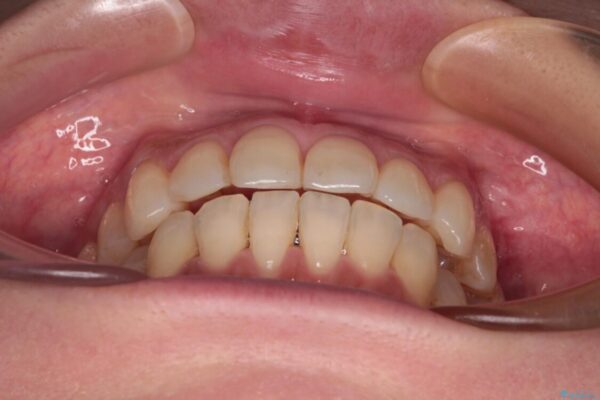

全体的なデコボコと、以前抜歯した歯のスペースを閉じた部分が気になるとのことで来院された患者様です。

左上第一大臼歯を抜歯した際に、スペースを閉じたそうですが、歯が傾斜してものが挟まって不快とのことでした。

インビザライン矯正で全体の歯列と整えるとともに、左上第一大臼歯部にはスペースを作り、インプラントによる補綴治療を行うこととしました。

歯の傾斜が改善され、インプラントによるクラウンが装着されたことで、物が挟まることもなくなりました。

治療前

• インビザラインによる矯正治療と奥歯のインプラント治療 治療前画像